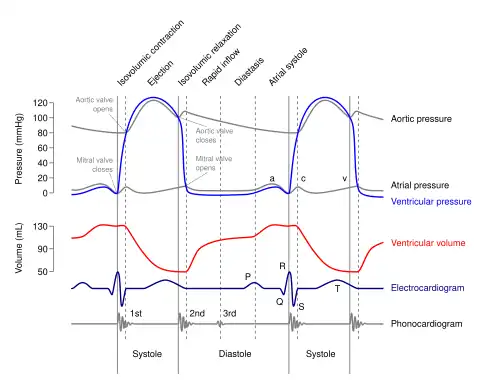

During systole, the ventricles contract, pumping blood through the body. During diastole, the ventricles relax and fill with blood again.

The left ventricle receives oxygenated blood from the left atrium via the mitral valve and pumps it through the aorta via the aortic valve, into the systemic circulation. The left ventricular muscle must relax and contract quickly and be able to increase or lower its pumping capacity under the control of the nervous system. In the diastolic phase, it has to relax very quickly after each contraction so as to quickly fill with the oxygenated blood flowing from the pulmonary veins. Likewise in the systolic phase, the left ventricle must contract rapidly and forcibly to pump this blood into the aorta, overcoming the much higher aortic pressure. The extra pressure exerted is also needed to stretch the aorta and other arteries to accommodate the increase in blood volume.

The right ventricle receives deoxygenated blood from the right atrium via the tricuspid valve and pumps it into the pulmonary artery via the pulmonary valve, into the pulmonary circulation.

Pressures

Red = aortic pressure

Blue = left ventricular pressure

Yellow = left atrial pressure.

Ventricular pressure is a measure of blood pressure within the ventricles of the heart.[13]

Left

During most of the cardiac cycle, ventricular pressure is less than the pressure in the aorta, but during systole, the ventricular pressure rapidly increases, and the two pressures become equal to each other (represented by the junction of the blue and red lines on the diagram on this page), the aortic valve opens, and blood is pumped to the body.

Elevated left ventricular end-diastolic pressure has been described as a risk factor in cardiac surgery.[14]

Noninvasive approximations have been described.[15]

An elevated pressure difference between the aortic pressure and the left ventricular pressure may be indicative of aortic stenosis.[16]

Right

Right ventricular pressure demonstrates a different pressure-volume loop than left ventricular pressure.[17]